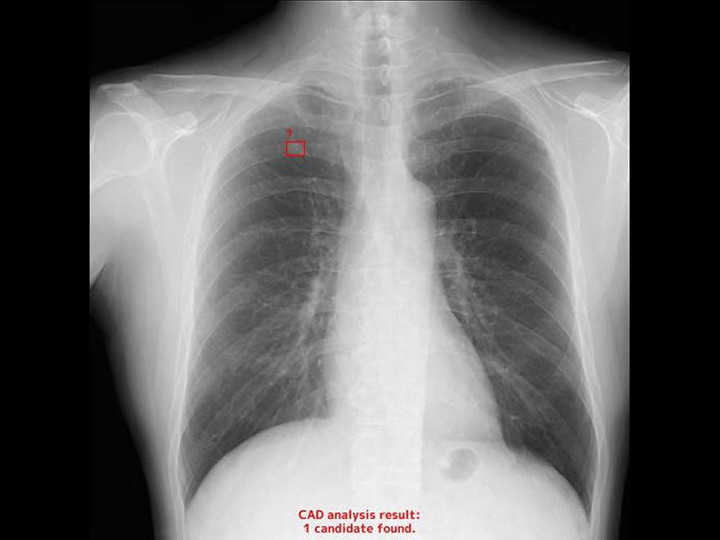

胸部CR×肺結節

EIRL Lung Nodule

胸部X線画像より、肺結節の形状に類似した領域を検出します

- クリニックで、ワンマン読影の補助として

- 検診で、膨大な読影の見落とし防止として

- 病院で、胸部が専門ではない診療科の先生の補助として

エルピクセル株式会社より提供を受けている医療機器「医用画像解析ソフトウェア EIRL X-ray Lung nodule」を搭載しております。